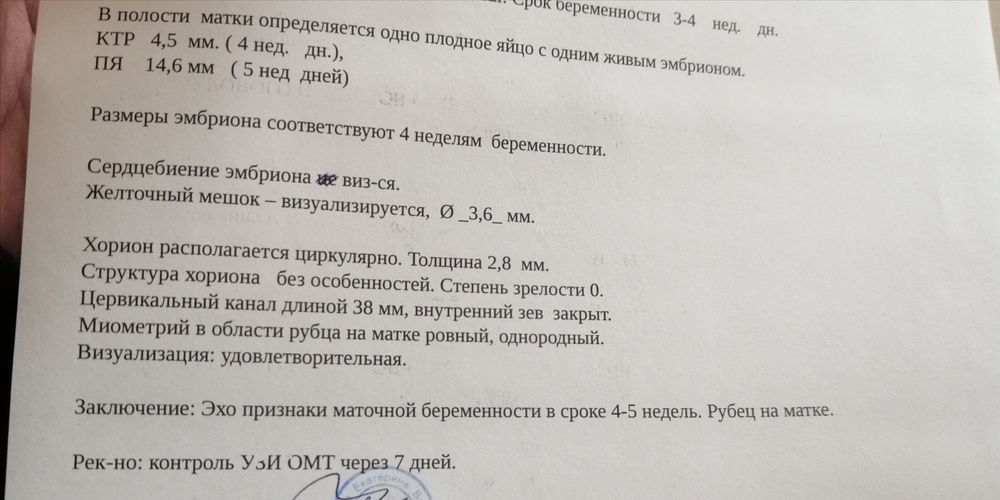

Всем доброго дня. Спасибо девочкам, кто вчера меня встряхнул и сказал бежать в больницу. Начались выделения(коричневатые, но не много) , вчера никак не могла вызвать скорую, нужно было доехать утром до работы, передать ключи. После этого ланью поскакала в ЖК. Так вот, после осмотра направили меня на дневной стационар. Перед этим сделали узи. Мне кажется я давно так не боялась (вдруг сказали бы что все...)

Но нет! Врач сказала, отслойки нет, пульсацию видит, скорей всего сердечко, но пока не понятно, маленькие мы ещё. Сегодня и в последующие дни:дюфастон 3р в день, витамины, покой, дротоверин в случае болей в животе. Завтра куча анализов, и по ним возможна корекция лечения.